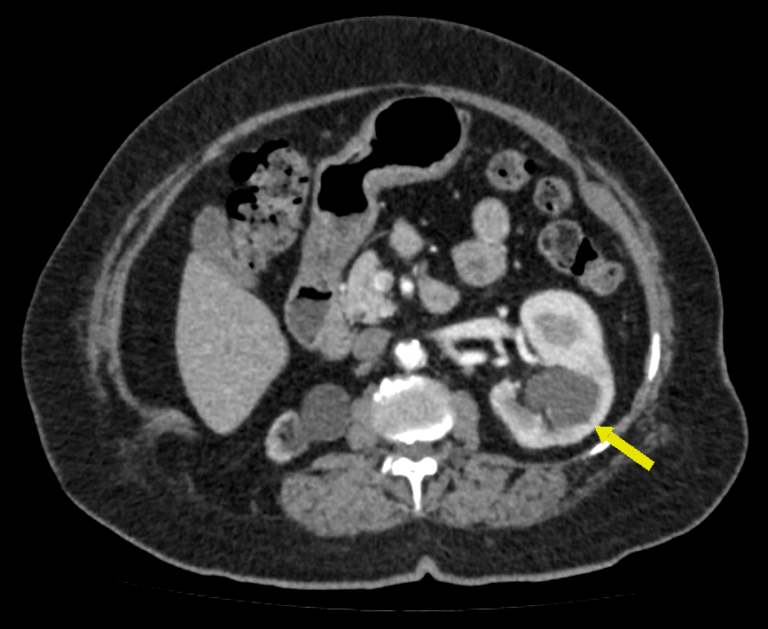

O exame permite avaliar as vias urinárias, sendo possível estudar os dutos que transportam a urina produzida pelos rins até a bexiga, para ser eliminada.

Na urotomografia o uso do contraste é obrigatório. A solução de contraste iodado é administrada por via endovenosa e distribui o contraste entre as estruturas com fluxos sanguíneos, realçando as estruturas hipervascularizadas, mostrando, por exemplo, tumores ou processos inflamatórios.